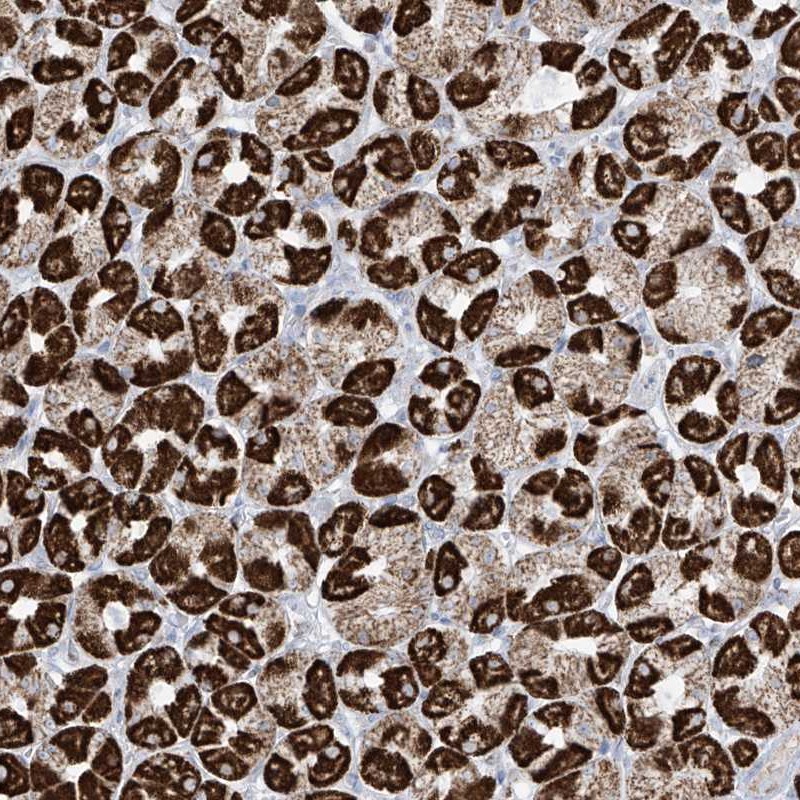

Immunohistochemical staining of human stomach shows strong cytoplasmic positivity(granular pattern) in parietal cells.